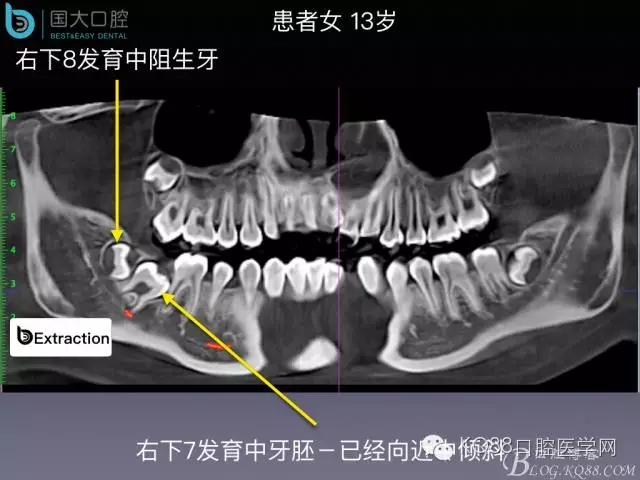

阻生牙的預(yù)防性拔除